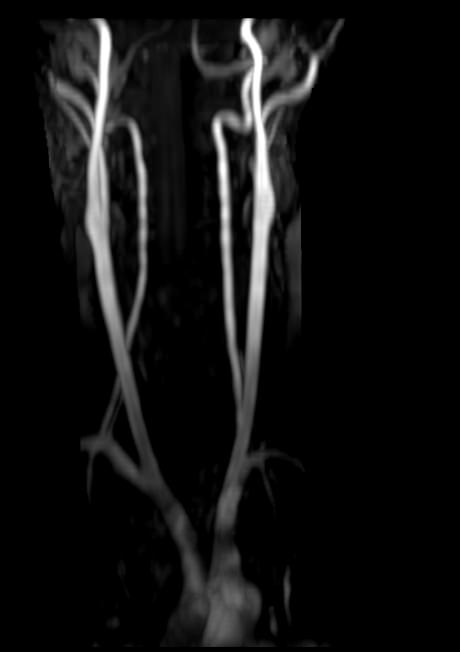

В клинике «Доступная медицина» проводится комплексное исследование: МР-ангиография шеи и головного мозга на новейшем высокопольном томографе экспертного уровня TOSHIBA VANTAGE TITAN 1,5 Тесла, который создает изображения сосудистой системы превосходного качества, что позволяет проводить точную диагностику и назначать пациенту своевременное лечение. МР-ангиография проводится в стандартном режиме без использования контраста.

- Суть исследования МРТ сосудов шеи и головного мозга

Суть исследования МРТ сосудов шеи и головного мозга

Для обнаружения заболеваний шеи, зачастую доктора назначают особые технологии проверки, например Доплер или рентген-анализ. Но бывают ситуации, связанные с вероятностью наличия в теле пациента аномальных процессов, происходящих в мягких тканях, тогда врачи выписывают направление на прохождение МРТ сосудов шеи. Подобное обследование показывает даже самые мелкие и незначительные изменения.